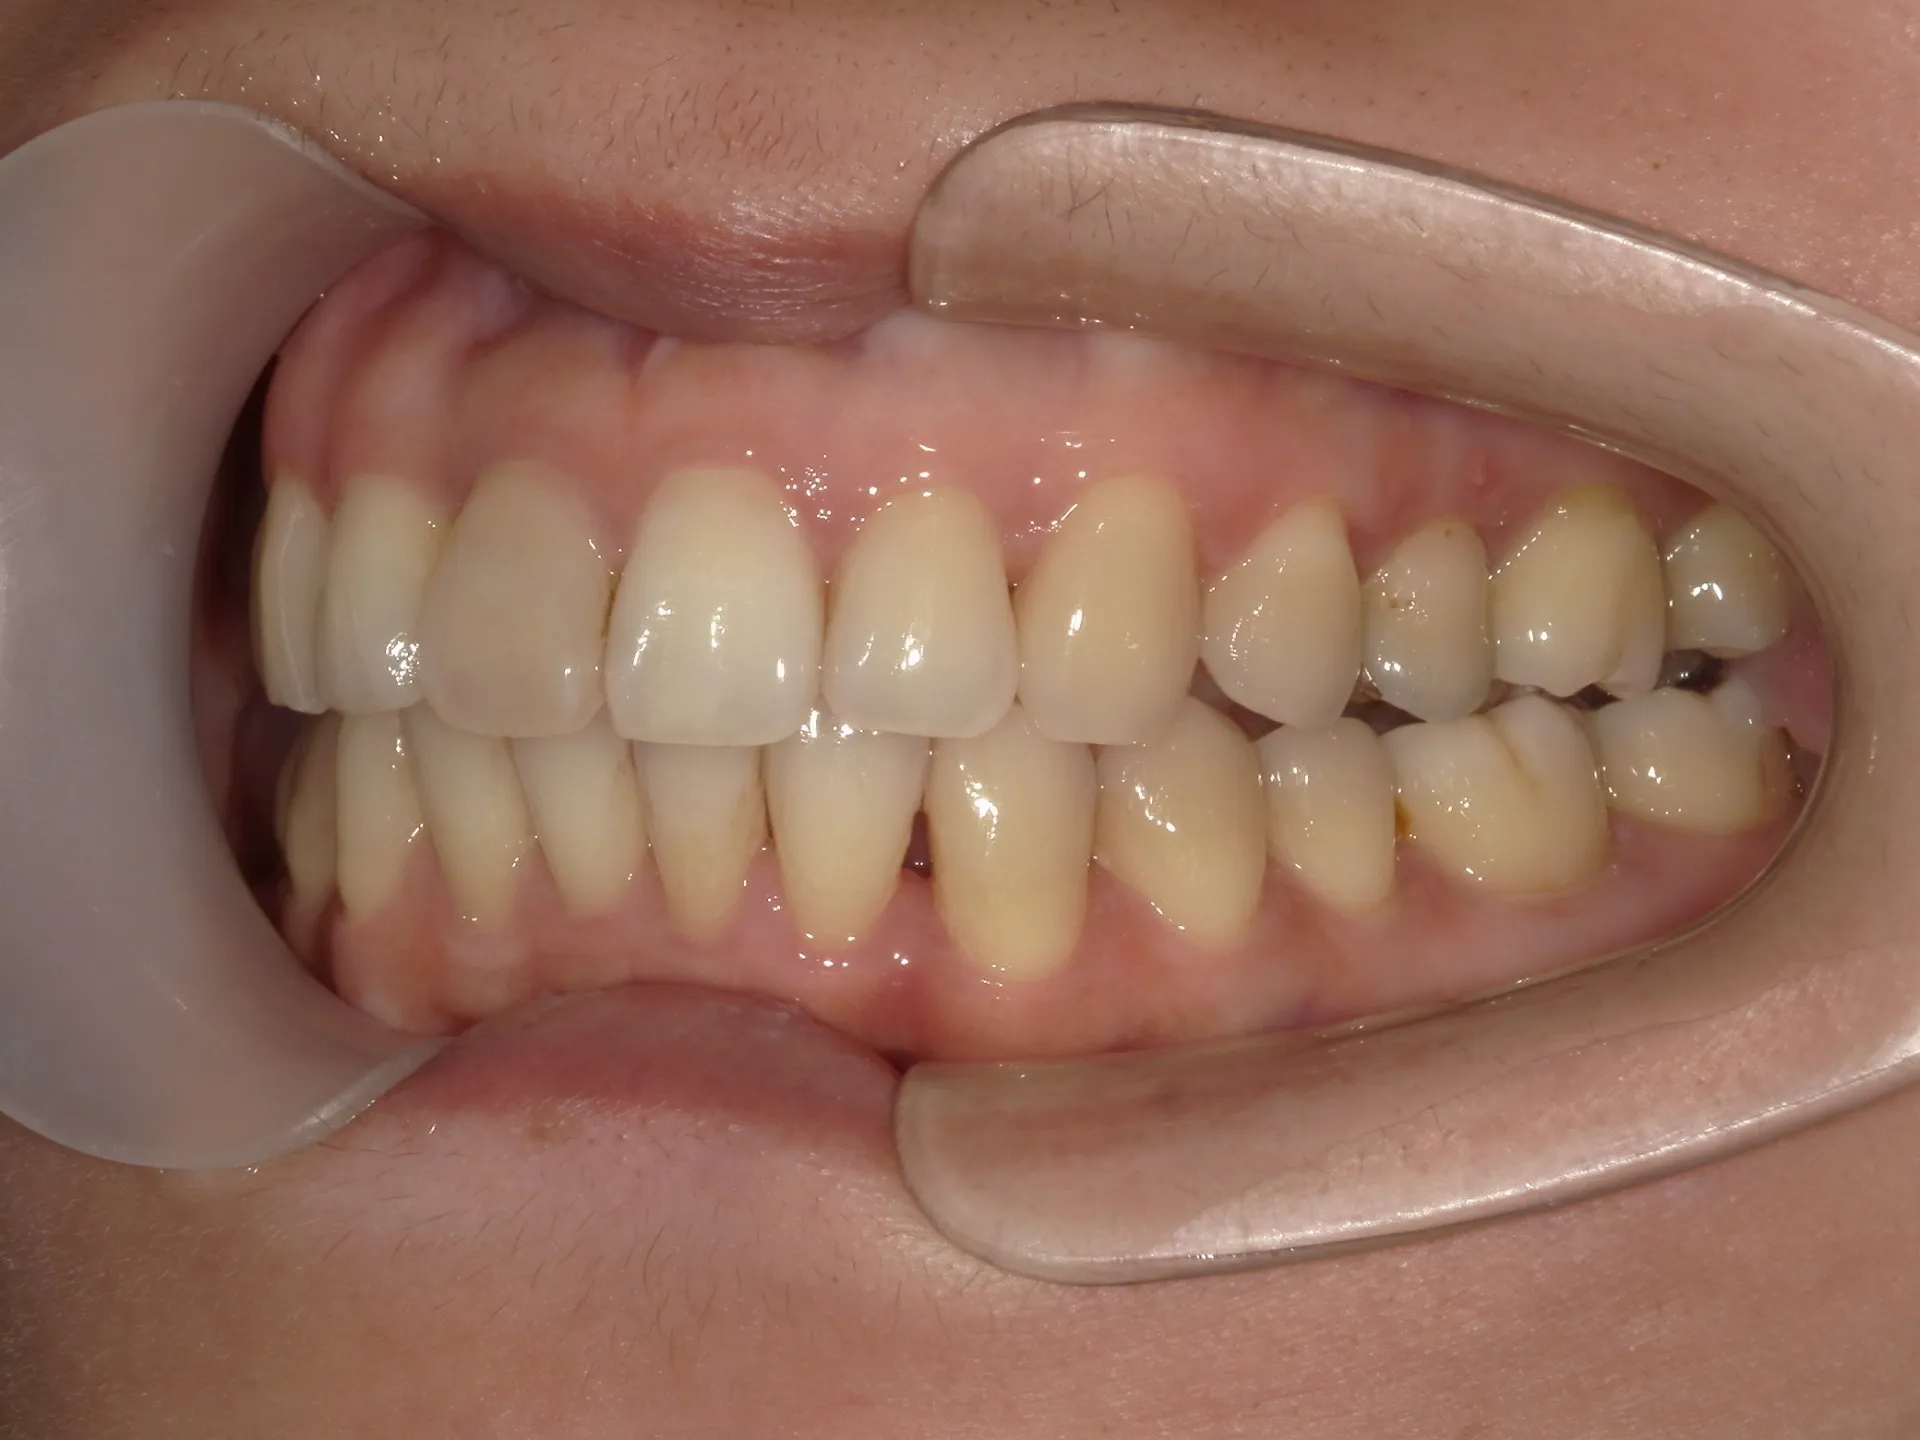

今回はねじれてしまった前歯の矯正治療をインビザラインというマウスピース矯正で治療した症例をご紹介いたします。